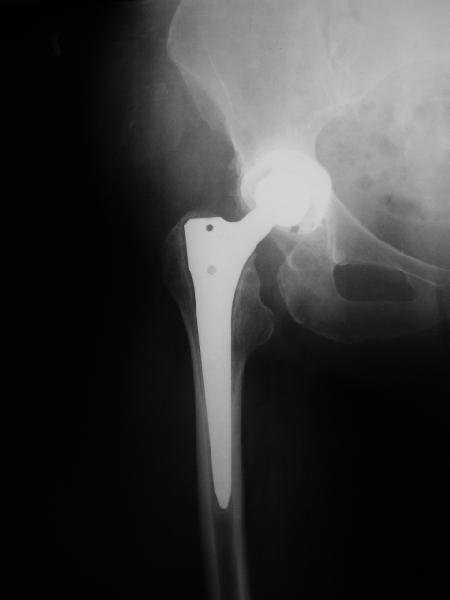

24 апреля 2005 г. правый сустав профиль (тут и болит)

С выбором имплантата можно не согласиться, но скорее всего просто поставили то, что было в наличии. :( Вертлужный компонент установлен

слишком медиально. По представленным рентгенограммам нельзя исключить нарушение целостности дна вертлужной впадины. Даже если в данным момент нестабильности нет, то она обязательно возникнет и скорее всего, создаст

На представленных Р-граммах явных признаков нестабильности эндопротеза нет. Чашка хоть и медиализирована, но стоит так же, как и 3 года назад и остеолиза нет. Есть остеолиз вокруг проксималного отдела ножки, но линия тонкая и не захватывает дистальный отдел. Судя по клинике, можно думать о травме (отрыв) ягодичных мышц в